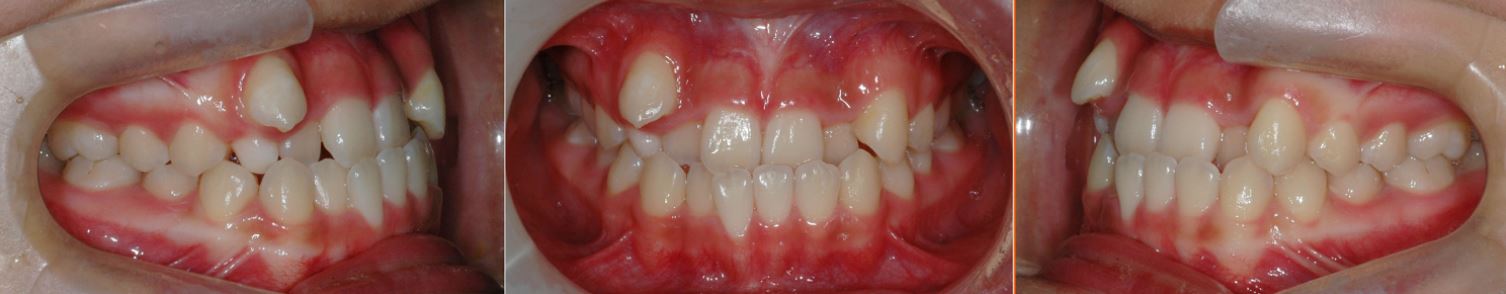

연구 대상 중 일란성 쌍둥이의 경우 유전자가 100% 동일하므로 동일한 치열 양상을 보일 것으로 예상했으나, 흥미롭게도 치열의 양상이 거울을 보듯 대칭적으로 나타났다. [그림 3]은 일란성 쌍둥이의 치열 상태로, 일란성 쌍둥이 중 한 명은 상악의 왼쪽 송곳니가 튀어나와 비뚤거리고, 다른 한 명은 반대쪽인 오른쪽 송곳니가 튀어나와 있는 것을 볼 수 있다. 아마도 자궁 내에서 서로 반대쪽에 대칭으로 위치하며 자라서 거울상(mirror image)을 보이는 것으로 추측된다고 연구팀은 설명했다.